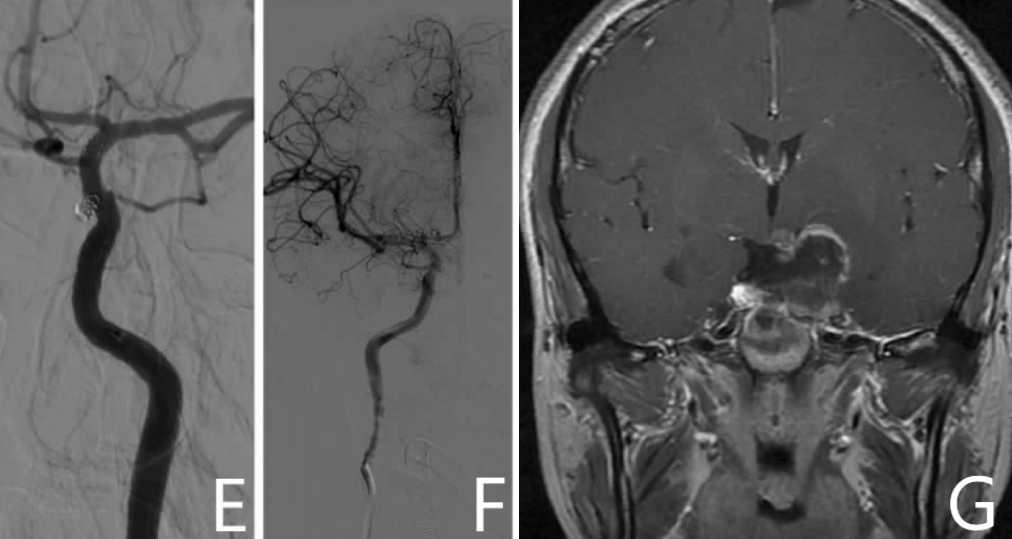

经科室讨论,决定先行双侧颈内动脉眼动脉段动脉瘤栓塞术(图3E,F)。手术顺利,暂出院。术后三个月DSA再次评估,显示动脉瘤填塞完全,无残留。逐再入院二期行内镜下经鼻蝶垂体腺瘤切除术(图3G)。

图3. E,F:术后造影显示双侧颈内动脉眼动脉段动脉瘤栓塞完全。G:术后肿瘤完全切除。

患者术后2年每隔6个月行垂体MRI检查显示无肿瘤复发,术后1年行DSA检查显示无动脉瘤复发。